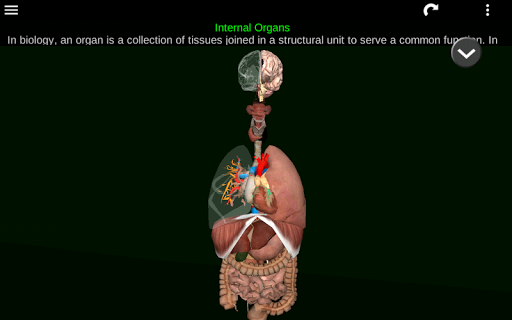

Internal Organs 3D Anatomy 3.4

Internal Organs 3D Anatomy 3.1

Organs 3D Anatomy 2.0.12